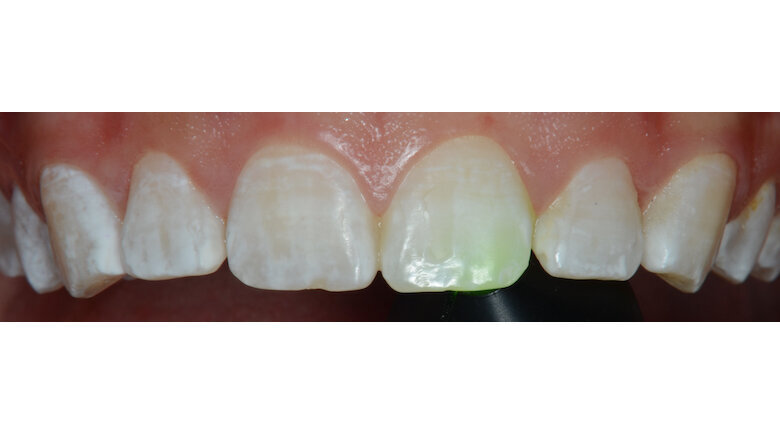

Uno de los factores más importantes de nuestra profesión es el diagnóstico adecuado, para saber qué tipo de procedimiento realizaremos. La transiluminación en estos casos es de suma importancia para identificar la profundidad de la lesión. Si colocamos un lente de color verde o naranja (Valo) detrás del diente afectado, veremos cómo algunas manchas llegan a desaparecer y otras no (Fotos 3 y 5). Las regiones donde llegan a desaparecer son las que tendrían menos de 200µ, donde la pasta abrasiva llegaría a remover las manchas; en las otras áreas, donde tenemos una mayor profundidad, necesitaríamos más aplicaciones o realizar una pequeña abrasión con fresas de diamante fino y luego pulir con pastas diamantadas (Diamond Polish 1µ) y ruedas de goma impregnadas en diamante (Jiffy Natural) (Foto 8).